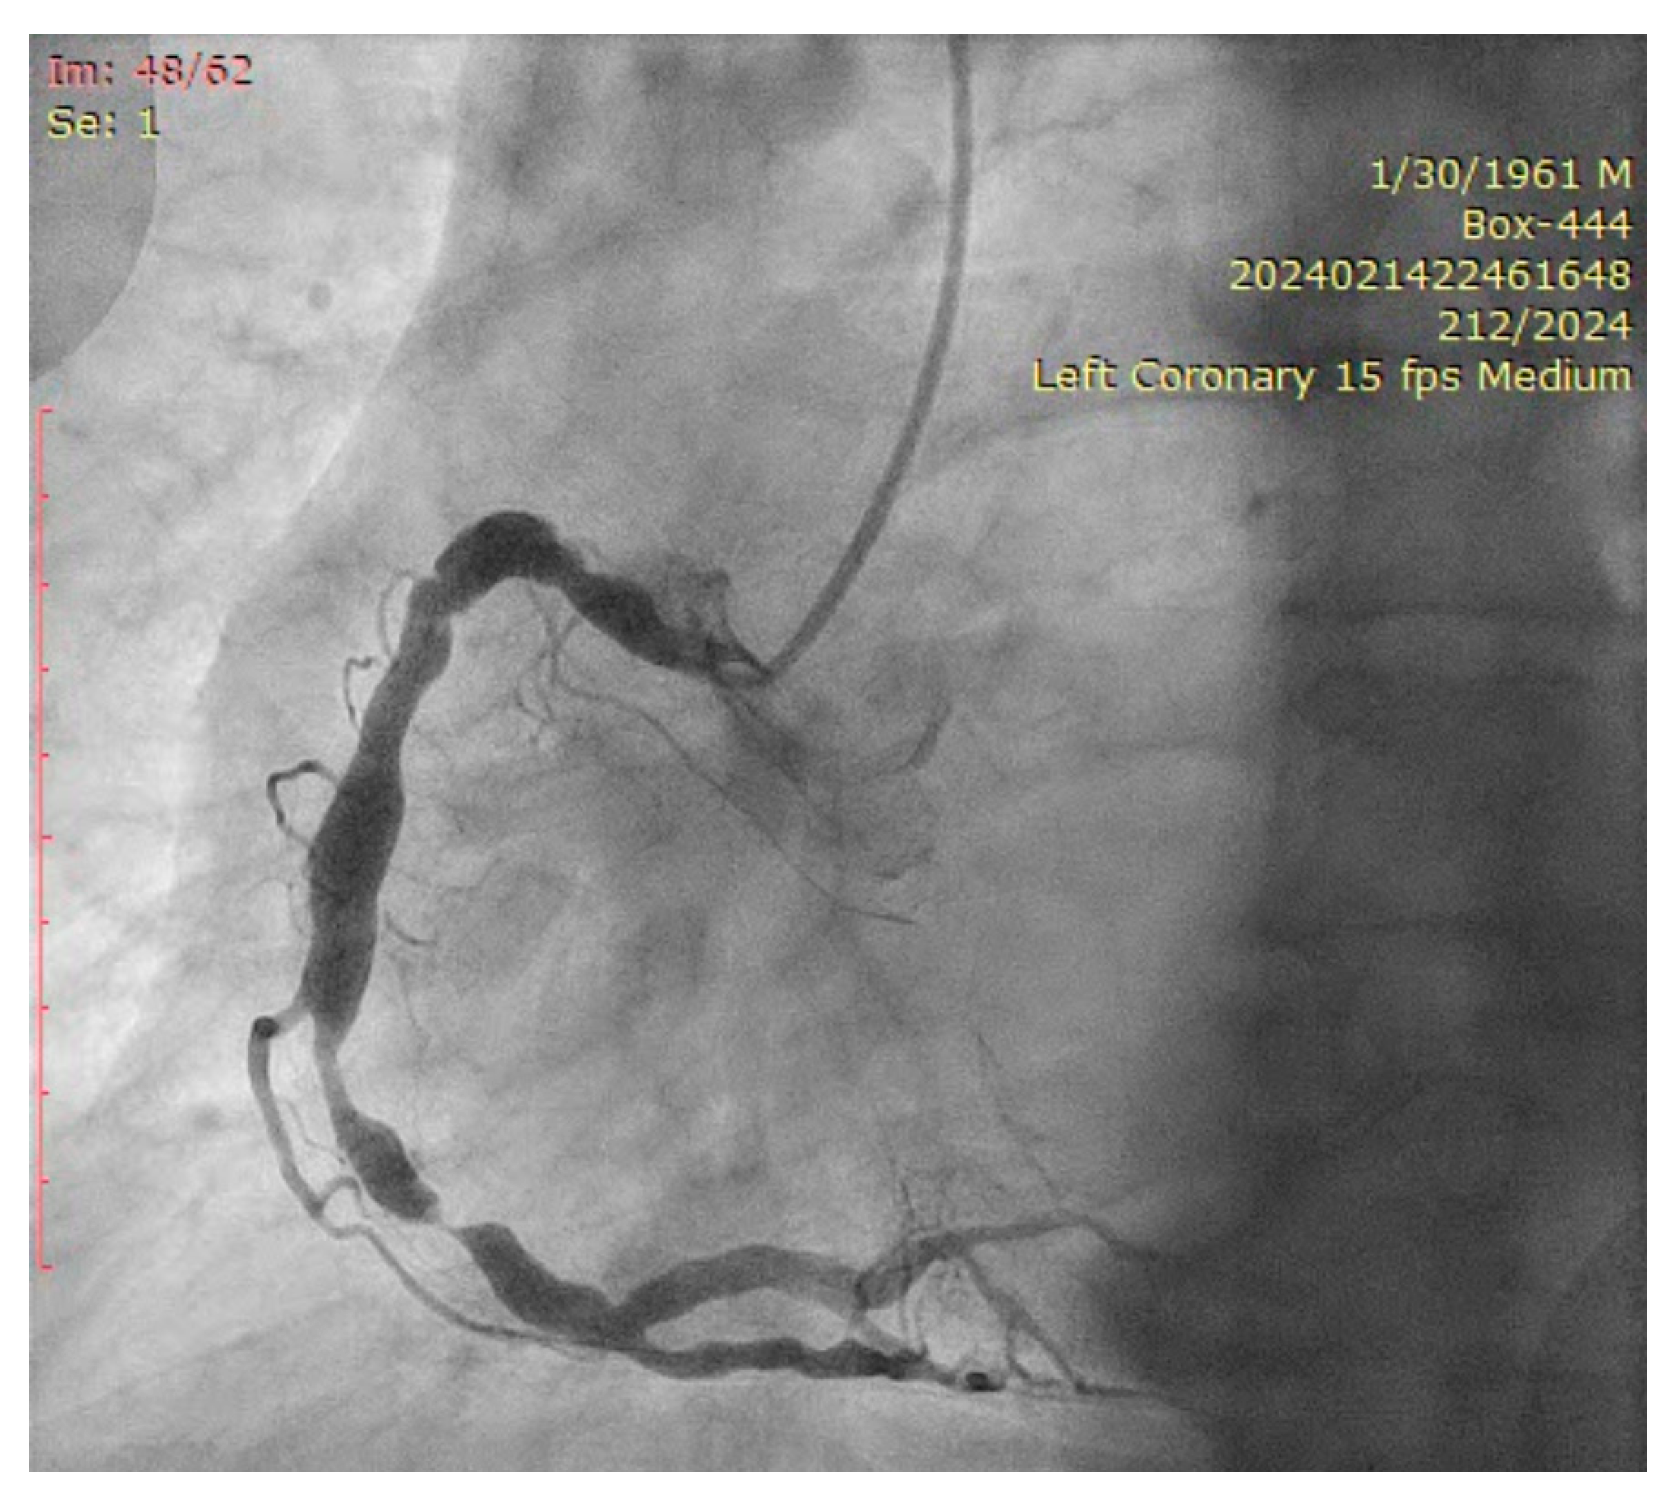

The ostium of left anterior descending artery (LAD) presented a 75% stenotic lesion, with the proximal segment displaying a 90% lesion (Figure 3). The left circumflex artery (LCX) revealed a 75% stenotic lesion of the ostium and tapered disease of its distal segment with areas of ectasic disease, with the ostium of the ramus intermedius (RI/RM) showing a 75% lesion (modified Medina classification 0-1-1-1 [4]) (Figure 4, Figure 5, Figure 6, Figure 7, Figure 8, Figure 9 and Figure 10).

Figure 3.

Left coronary artery (Right anterior oblique caudal (RAO) caudal view).